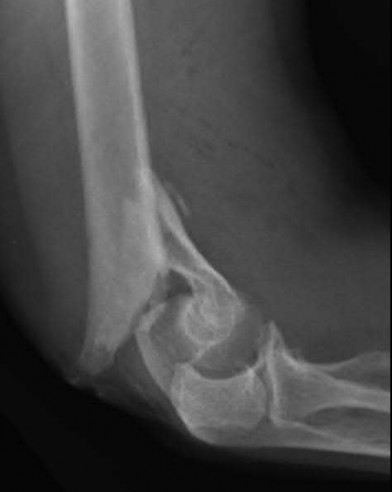

Question 14:

A 65-year-old male presents with deteriorating handwriting, dropping objects, and an unsteady, broad-based gait. On physical examination, flicking the volar nail of the middle finger results in an involuntary flexion reflex of the thumb and index finger. What is the name of this sign and its corresponding pathology?

Options:

- Wartenberg's sign - Ulnar neuropathy

- Hoffman's reflex - Cervical myelopathy

- Babinski reflex - Upper motor neuron lesion

- Lhermitte's sign - Multiple sclerosis

- Froment's sign - Anterior interosseous nerve syndrome

Correct Answer: Hoffman's reflex - Cervical myelopathy

Explanation:

The Hoffman's reflex is elicited by flicking the nail of the middle finger; a positive response is flexion of the IP joint of the thumb and index finger. It indicates an upper motor neuron lesion, classically cervical spondylotic myelopathy. Wartenberg's sign is the abducted posture of the small finger due to ulnar neuropathy. Lhermitte's sign is shock-like sensations down the spine with neck flexion. Froment's sign tests for ulnar nerve palsy (adductor pollicis weakness).